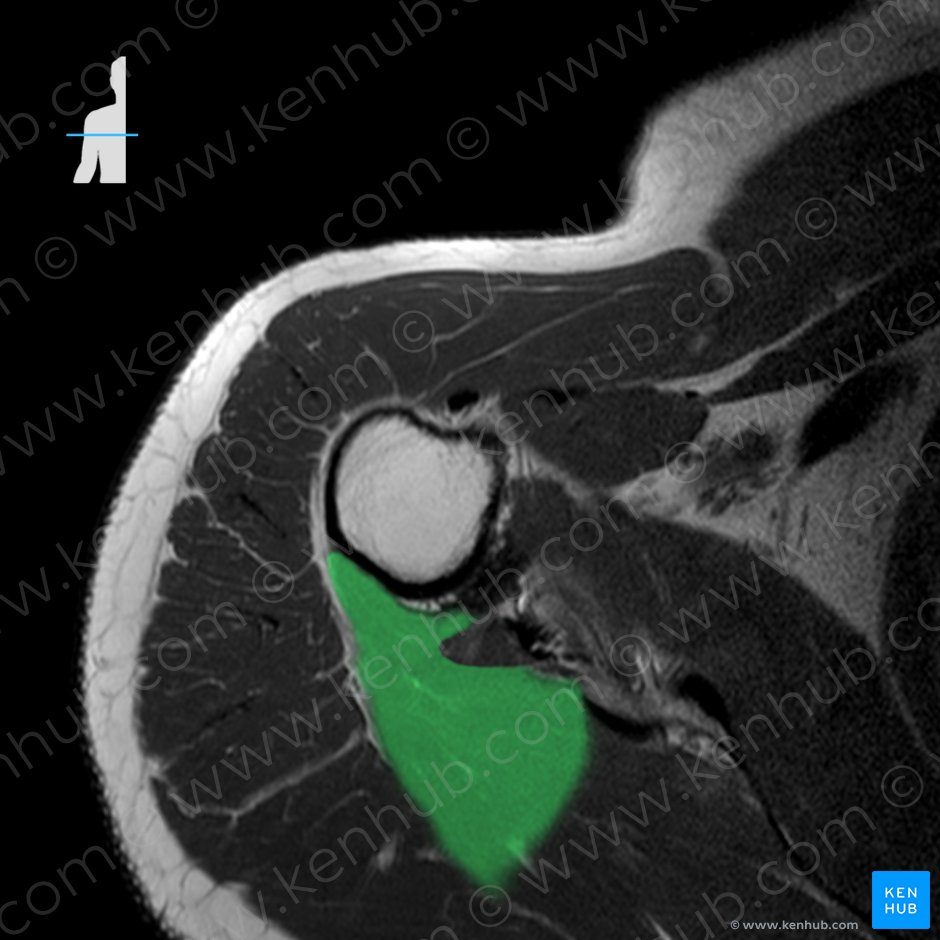

2. 견갑하근(Subscpularis, 어깨밑근)

origin : 견갑골 전면의 견갑하와

(Subscapular fossa of scapula)

insertion : 상완골 소결절

(Lesser tubercle of humerus)

function : Shoulder joint: Arm internal rotation

Stabilizes humeral head in glenoid cavity

견갑하근은 어깨의 내회전, 내전에 관여하며

4개의 회전근개 중 가장 크고 두꺼우며 강한힘을 내는 근육입니다.

견갑골의 앞쪽에 위치하여, 침습적 접근이 어려운 부위로

마사지나 테이핑 등을 통해 접근합니다.

견갑하근의 경우 어깨 후면에서 팔, 주관절 부위로 방사통이 나타납니다.

손목에 띠 같은 부위로 방사통이 나타나는 것이 특징인데,

대부분 손등이 손바닥보다 압통과 통증시 심합니다.극하근과의 차이점은,

엄지손가락을 위로한 상태로 외전시 통증이 심화됩니다.